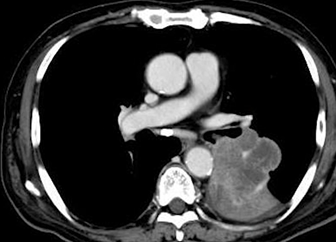

ちなみにCT所見は無気肺(腫瘤の場合造影効果(血管)は映らない)でしたが、無気肺に至る何かしらの原因(Tbや肺癌や誤嚥など)があると推定され、それはそれで精査が必要な所見です。